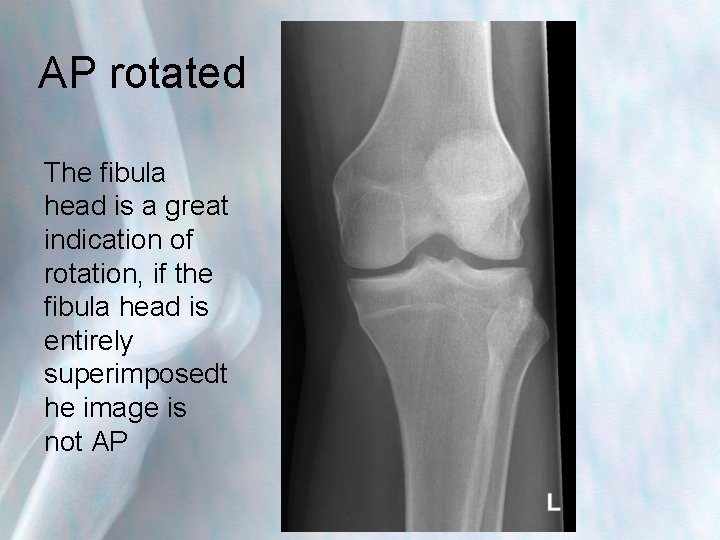

AP rotated The fibula head is a great indication of rotation, if the fibula head is entirely superimposedt he image is not AP